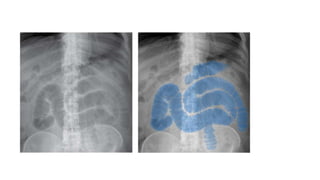

1. RIGLER’S SIGN – DOUBLE

When gas is present on both

sides of the intestinal wall .

Sometimes ,

two loops of

bowel lying

next to each

other may

mimic this

sign. This

can be

identified by

haustra or

valvulae.